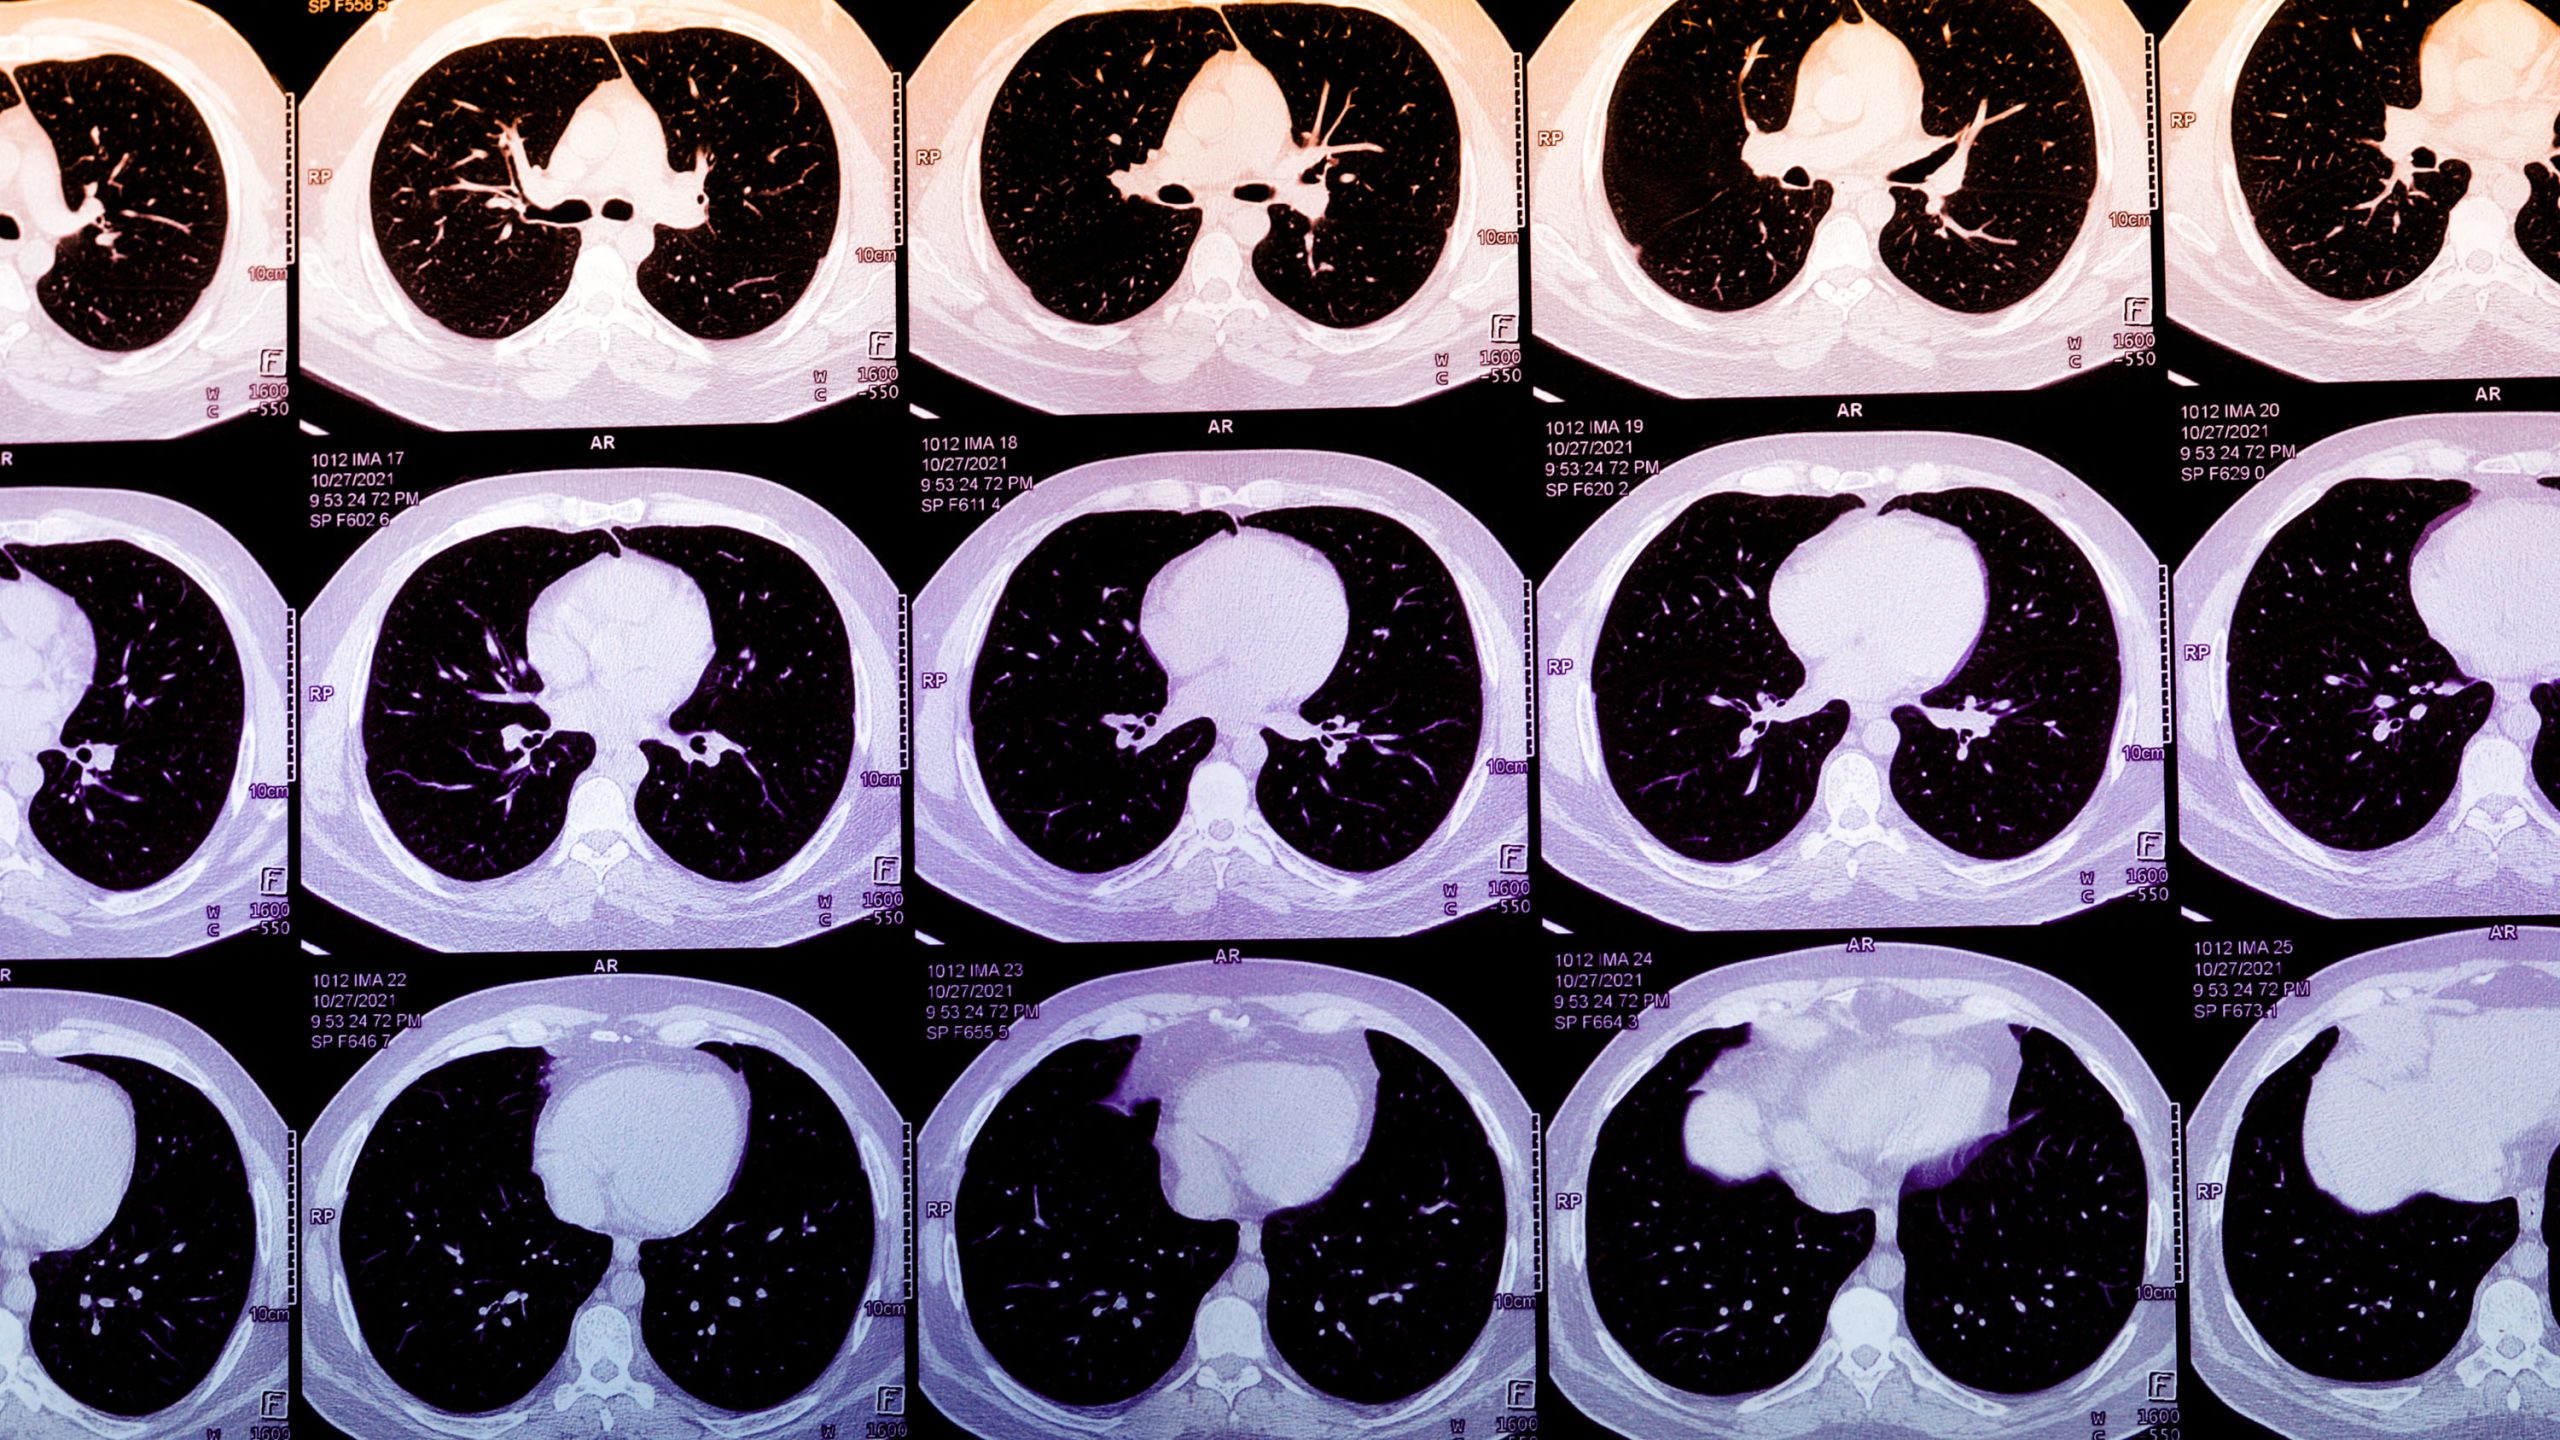

他の目的で撮影されたCTスキャンから、AIが心筋梗塞の兆候となる冠動脈石灰化を自動検出する技術が複数の企業から登場している。年間2000万人のスキャンから見逃されていたリスクを発見できる可能性がある一方、AIが疾病を定義する時代の複雑な課題も浮上している。 by Vishal Khetpal2025.10.23

心臓病学の現代的な驚異的技術をもってしても、我々は誰が心筋梗塞を起こすかを予測するのに苦労している。多くの人はスクリーニングをまったく受けていない。現在、バンカーヒル・ヘルス(Bunkerhill Health)、ナノックスAI(Nanox.AI)、ハートラング・テクノロジーズ(HeartLung Technologies)といったスタートアップ企業が、AIアルゴリズムを用いて数百万件のCTスキャンから心疾患の初期兆候をスクリーニングしている。この技術は公衆衛生にとって画期的な進展となる可能性があり、従来のツールを応用して、表面的には健康に見える心筋梗塞の高リスク患者を特定できるかもしれない。しかし、その大規模な有効性はまだ証明されておらず、導入方法や疾患の定義に関する複雑な問題も提起している。

昨年、推定2000万人の米国人が、交通事故などの事象の後や肺がんスクリーニングのために胸部CTスキャンを受けた。これらのスキャンでは、心筋梗塞リスクのマーカーである冠動脈石灰化(CAC)の証拠が頻繁に示されるが、骨損傷、生命に関わる内部外傷、がんの除外に焦点を当てた放射線科レポートでは見過ごされるか、まったく言及されないことが多い。

冠動脈石灰化は胸部CTでしばしば確認され、その濃度は主観的に記述されることが多い。通常、個人のCACスコアを定量化するには、心臓に特化したCTスキャンが必要である。しかし、日常的な胸部CTからCACスコアを算出するアルゴリズムは、この指標へのアクセスを飛躍的に拡大する可能性がある。実際には、これらのアルゴリズムを用いることで、異常に高いスコアを持つ患者とその主治医に警告を発し、さらなる治療行動を促すことがで …